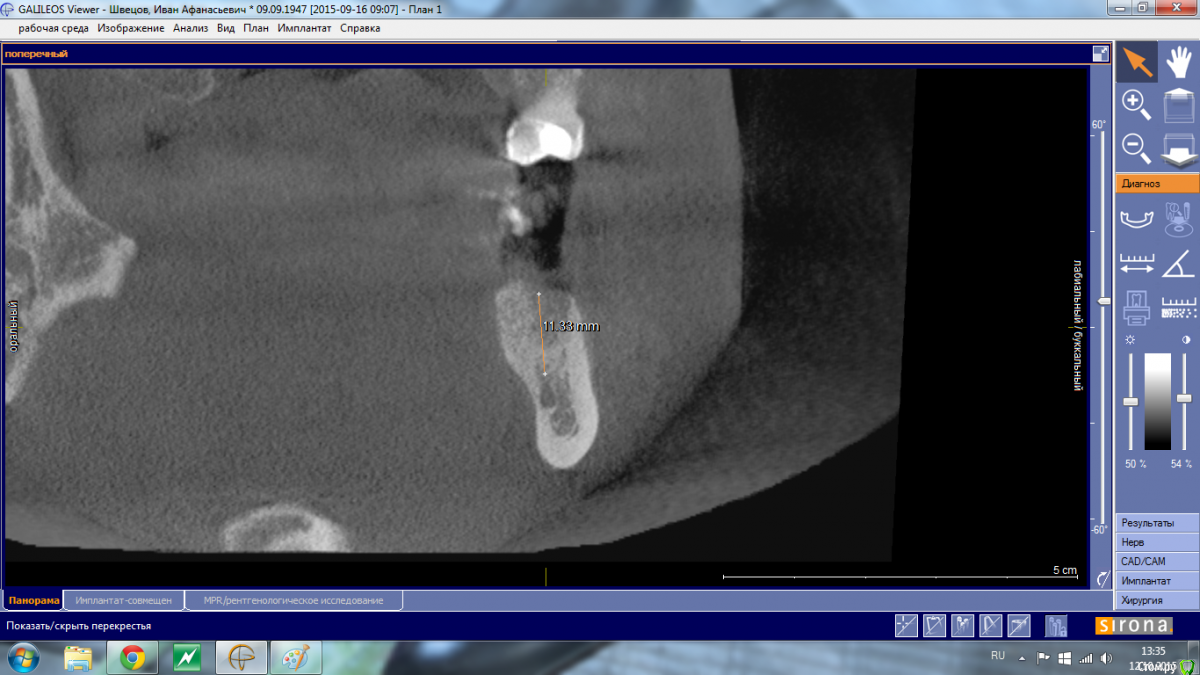

Shakirbura Опубликовано 12 октября, 2015 Автор Поделиться Опубликовано 12 октября, 2015 Снимок до имплантации.Сверло уперлось в 8-9 мм, что для меня было неожиданностью Ссылка на комментарий

АнтонТЛТ Опубликовано 13 октября, 2015 Поделиться Опубликовано 13 октября, 2015 Снимок до имплантации.Сверло уперлось в 8-9 мм, что для меня было неожиданностьюСкорее всего уперлись в подъязычное поднутрение, резцы с парестезией? 2 Ссылка на комментарий

Shakirbura Опубликовано 13 октября, 2015 Автор Поделиться Опубликовано 13 октября, 2015 Скорее всего уперлись в подъязычное поднутрение, резцы с парестезией?Семент от места имплантации до центра с парестезией. Имплантацию проводил под инфильтрационной анестезией, в момент проваливания пациент не сильно отреагировал. Говорит, что "как будто губу чем то задели". Ссылка на комментарий

АнтонТЛТ Опубликовано 13 октября, 2015 Поделиться Опубликовано 13 октября, 2015 Давайте контрольный снимок, если имплантат далеко от канала, то скорее всего травма + гематома (само пройдет), если имплантат в канале, то вынимать. 3 Ссылка на комментарий